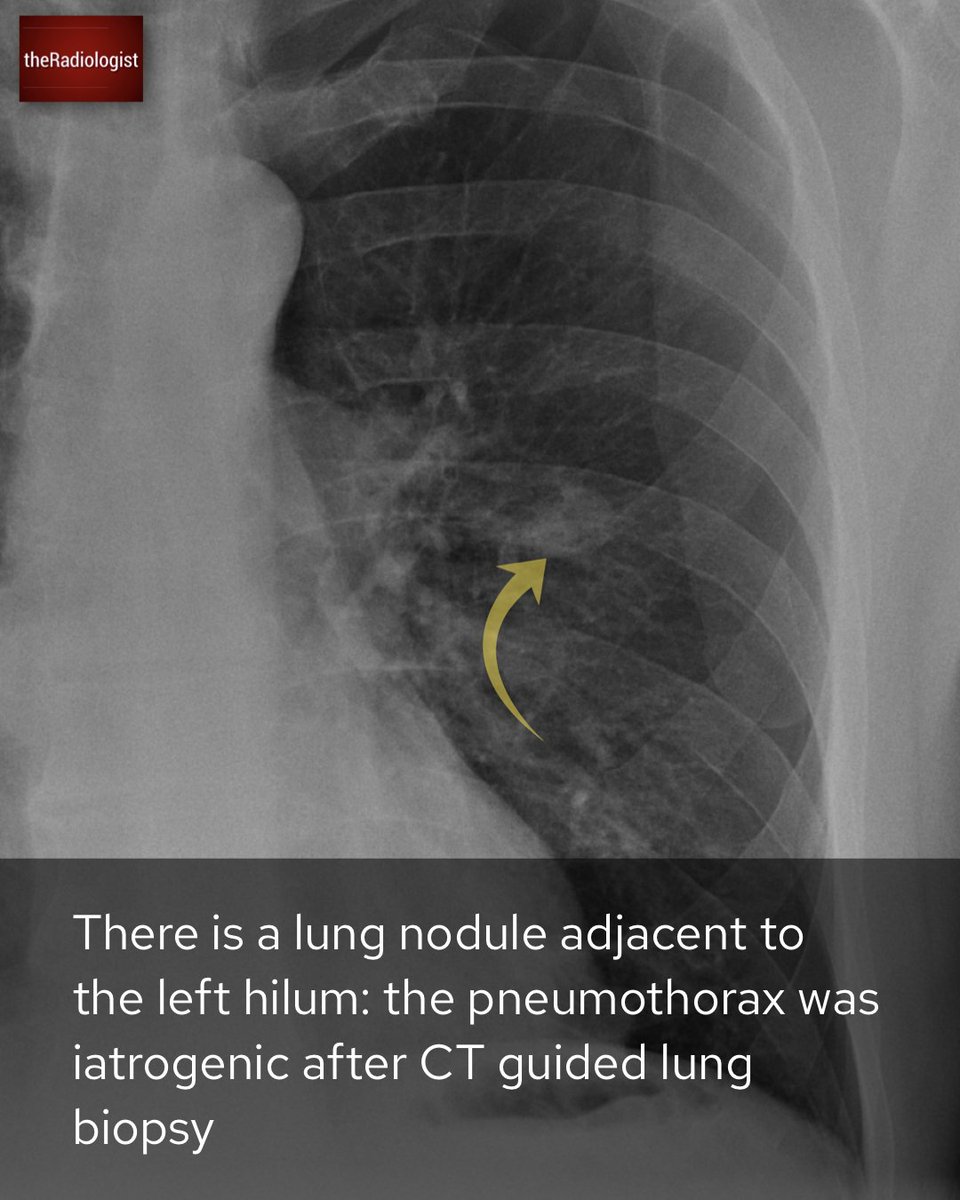

A male in his 40s with an underlying medical condition presents with a cough: case explanation